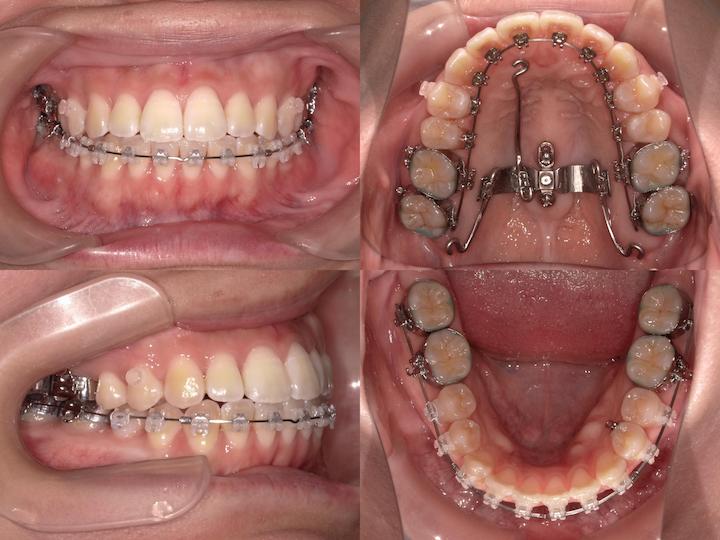

症例概要

本症例は、叢生および口唇部の突出感を主訴とする患者様に対し、ハーフリンガル矯正装置(上顎舌側・下顎唇側)を使用して治療を行いました。

下顎骨の後方位を伴うハイアングル症例であったため、上顎大臼歯の圧下を治療計画に組み込み、下顎骨のアンチクロックワイズローテーション(反時計回り回転)を誘導することで、口唇部の突出感改善と良好な咬合関係の確立を目指しました。

初診時の口腔内所見および頭部X線規格写真分析より、以下の所見が認められました。

・上下顎前歯部の叢生

・口唇部の突出感

・AngleⅠ級臼歯関係(良好な臼歯関係)

・下顎骨の後方位(ハイアングル症例)

・下顎下縁平面角の増大

・上下左右第一小臼歯の抜歯による叢生の改善

・上顎大臼歯の圧下による下顎骨のアンチクロックワイズローテーション誘導

・AngleⅠ級臼歯関係の維持

上顎大臼歯の圧下により下顎骨を反時計回りに回転させることで、オトガイ部の前方移動と下顔面高の減少を図り、口唇部の突出感を改善する計画としました。

ハーフリンガル矯正装置を採用し、上顎は舌側矯正装置(リンガルブラケット)、下顎は唇側矯正装置(ラビアルブラケット)を使用しました。

・i-station(歯科矯正用アンカースクリュー)の植立:正中口蓋縫合部に植立し、上顎大臼歯の固定源として使用

・上顎大臼歯の圧下:i-stationからの圧下力により、上顎大臼歯を垂直的に圧下

・上顎大臼歯の固定:抜歯スペース閉鎖時の近心移動を防止し、AngleⅠ級臼歯関係を維持

・フルサイズワイヤーの使用:.018×.025インチTMA(チタンモリブデン合金)ワイヤーを使用し、臼歯部のみが選択的に圧下するように設計

・パラタルバーの装着:上顎大臼歯の幅径を維持し、歯列弓形態の安定を確保

・前歯部の垂直的位置の維持:大臼歯圧下時に前歯部が挺出しないよう、ワイヤーで適切にコントロール

治療結果

上顎大臼歯の圧下により下顎骨のアンチクロックワイズローテーションが誘導され、口唇部の突出感は著明に改善されました。

また、叢生も解消され、AngleⅠ級臼歯関係を維持したまま、機能的かつ審美的に優れた咬合状態を獲得することができました。

臼歯部の咬合も良好に保たれ、患者様からも高い満足度をいただいております。